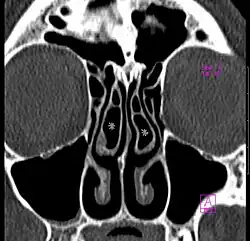

Concha bullosa

A concha bullosa is a pneumatized (air-filled) cavity within a nasal concha, also known as a turbinate.[1] Bullosa refers to the air-filled cavity within the turbinate.[1] It is a normal anatomic variant seen in up to half the population. Occasionally, a large concha bullosa may cause it to bulge sufficiently to obstruct the opening of an adjacent sinus, possibly leading to sleeping apnea or breathing disorder related to areas innervated by the trigeminal nerve.[2] In such a case the turbinate can be reduced in size by endoscopic nasal surgery (turbinectomy). The presence of a concha bullosa is often associated with deviation of the nasal septum toward the opposite side of the nasal cavity.[3]